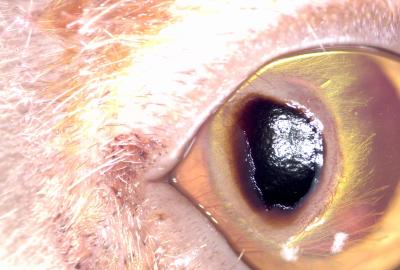

Na fotografiích je kočka před operací, v průběhu operace - lamelární keratektomie a 2 týdny po operaci.

Spastické entropium. Bolestivý stav na oku vedl k chlípení víčka a k dalšímu zhoršení stavu rohovky iritací chlupy. | Veterinární klinika Medipet Zlín

Tmavě pigmentovaný sekvestr se zánětem rohovky a výraznou vaskularizací. | Veterinární klinika Medipet Zlín